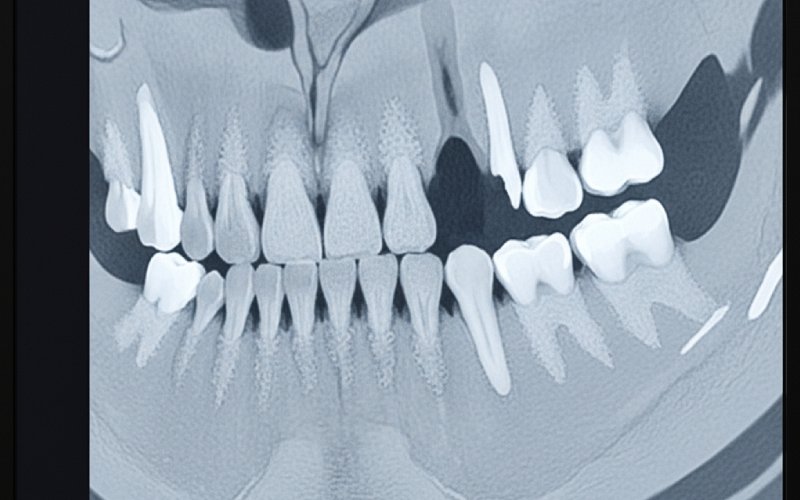

Hvornår du får et implantat, er en meget vigtig ting at tænke på, når du har mistet en tand. Din kæbeknogle har brug for noget at lave. Tandens rod holder knoglen i gang og i arbejde. Det holder den stærk og sund. Når du mister en tand, stopper det arbejde. Din krop begynder at tro, at der ikke længere er brug for knoglen. Det er derfor, mange tandlæger siger, at man skal få et tandimplantat så hurtigt som muligt efter tandtab.

Når en tand fjernes, begynder der at ske noget, der kaldes resorption. Det er et fint ord for en simpel idé. Uden denne stimulering fra tandroden begynder kæbebenet at skrumpe og blive svagere. Knoglen mister sin bredde og højde. Den mister også sin tæthed. Dette knogletab sker hurtigst i det første år efter en tandudtrækning. Men det fortsætter i årevis.

Dette knogletab kan ændre, hvordan dit ansigt ser ud. Det kan få dig til at se ældre ud. Det kan også få de nærliggende tænder til at løsne sig eller flytte sig til det forkerte sted. Knoglen kan blive så svag, at den ikke længere kan holde på et nyt tandimplantat uden hjælp. Det er hovedårsagen til, at folk bekymrer sig om, at det måske er for sent at få tandimplantater.

For at få et godt tandimplantat skal der være nok knogle. Knoglen skal være tyk nok til at holde tandimplantatet fast, mens det heler. Hvis din knogletæthed ikke er høj nok, kan implantatet placeres, men det er ikke sikkert, at det fungerer. Din tandlæge vil bruge særlige røntgenbilleder. De måler tætheden og mængden af din knogle. Det viser, om den kan bære et implantat.